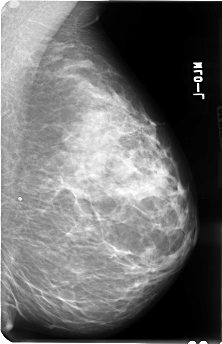

B_3040_1.RIGHT_MLO

RIGHT_MLO LINES 4824 PIXELS_PER_LINE 3112 BITS_PER_PIXEL 12 RESOLUTION 50 OVERLAY